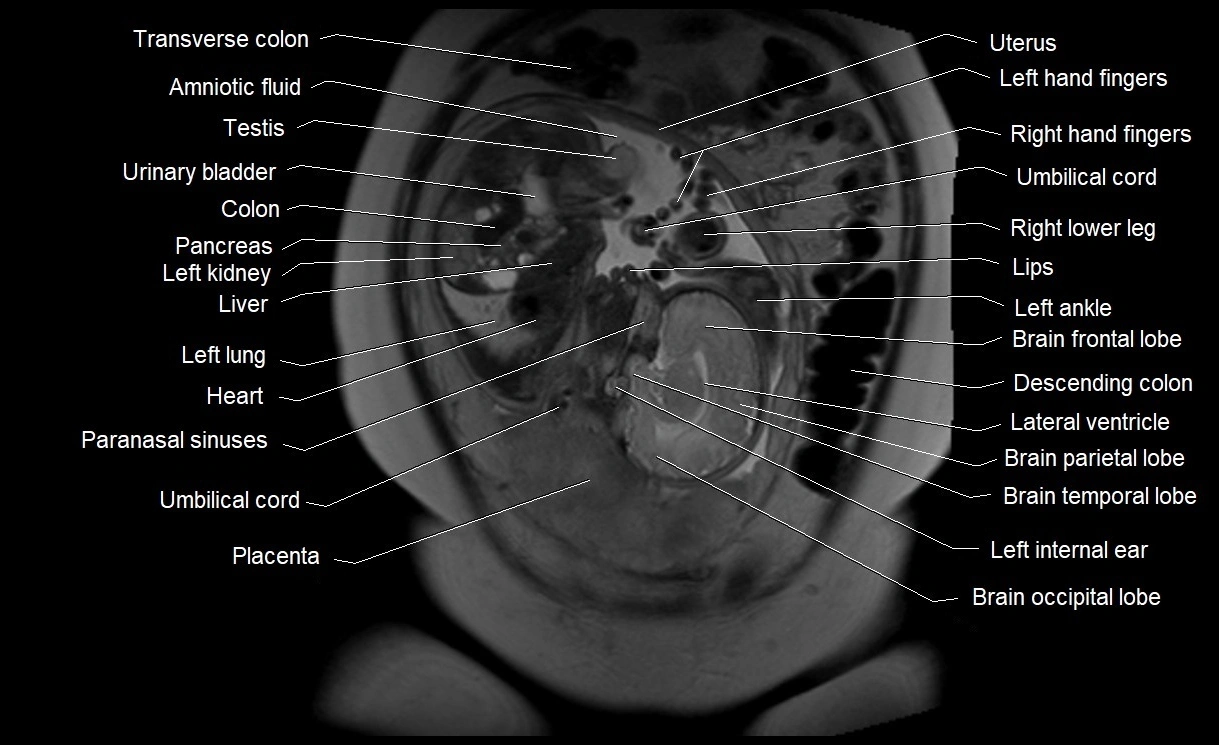

MRI Appearance

T2 HASTE (T2 GRE):

• Amniotic fluid shows very bright hyperintense signal

• Provides natural contrast against fetus and placenta

• Small particles (vernix) may appear as scattered hypointense foci within bright fluid

MRI image

image